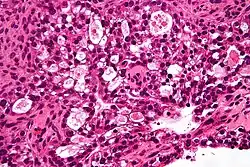

| Micrograph of a mucinous ovarian carcinoma stained by H&E | |

Mucinous

Mucinous tumors include mucinous adenocarcinoma and mucinous cystadenocarcinoma.[29]

Mucinous adenocarcinoma

Mucinous adenocarcinomas make up 5–10% of epithelial ovarian cancers. Histologically, they are similar to intestinal or cervical adenocarcinomas and are often actually metastases of appendiceal or colon cancers. Advanced mucinous adenocarcinomas have a poor prognosis, generally worse than serous tumors, and are often resistant to platinum chemotherapy, though they are rare.[29]